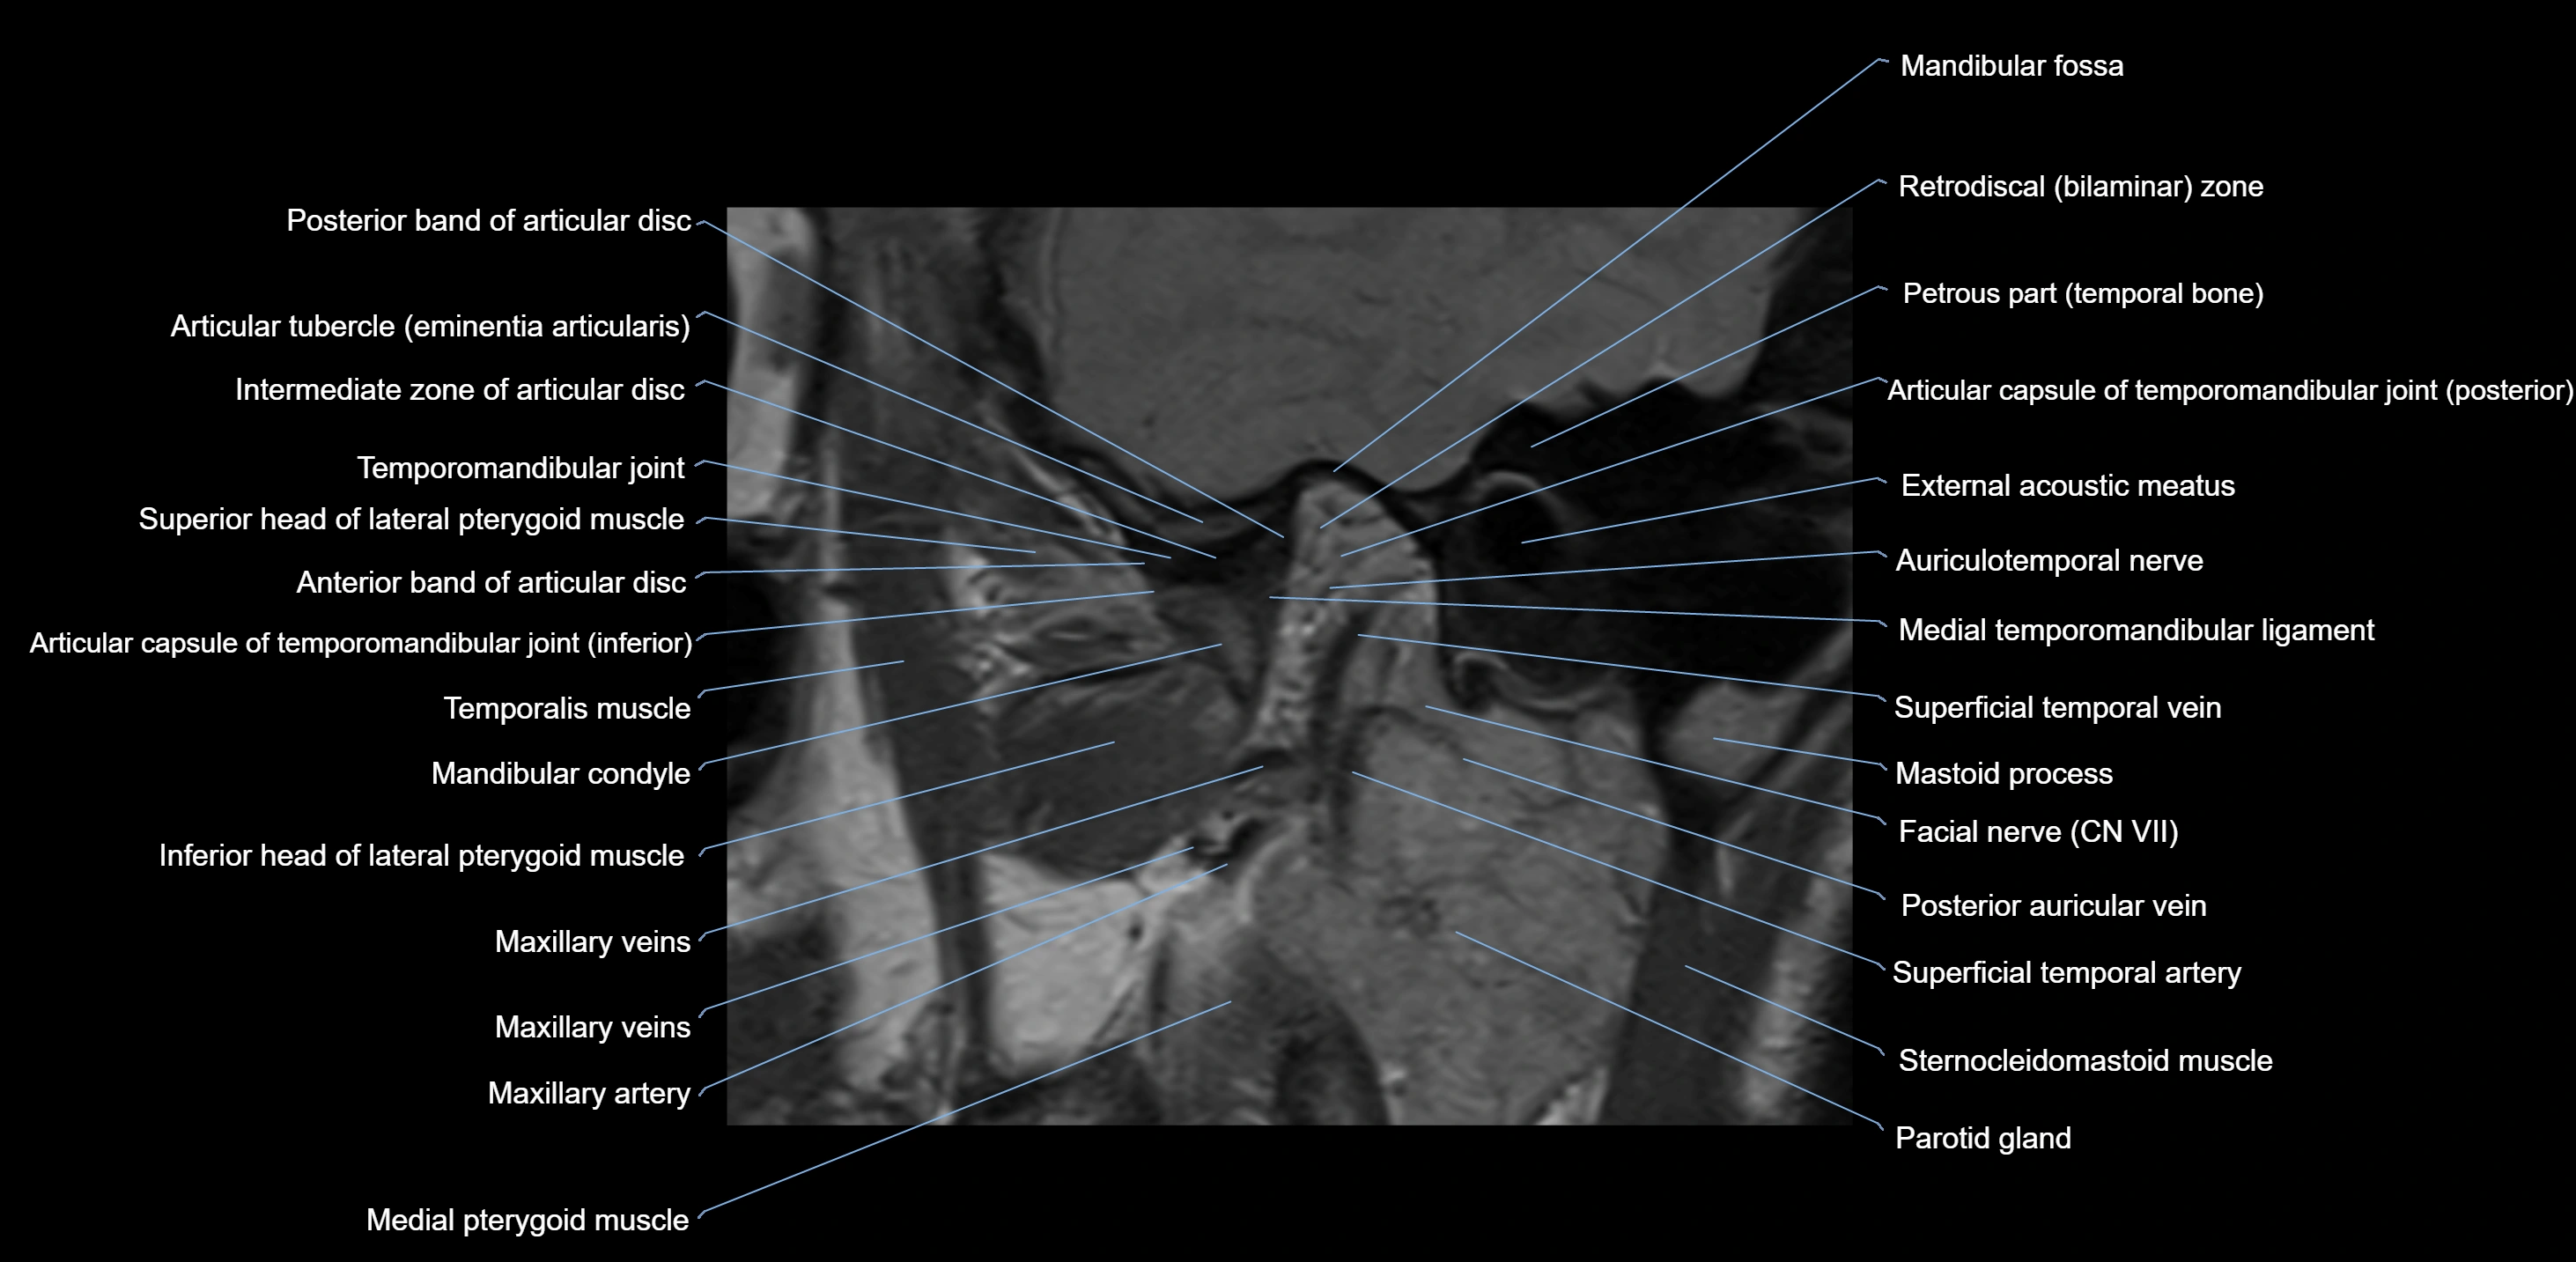

MRI appearance

T1-weighted images:

• Cortical bone: Low signal intensity

• Cancellous marrow: Intermediate to high signal depending on fatty content

• Teeth: Signal void structures

• Adjacent soft tissues: Normal gingiva and oral mucosa signal

T2-weighted images:

• Cortical bone and teeth: Low signal

• Marrow: Intermediate signal